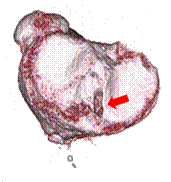

腱を移植するために長方形に作成した骨孔

再建された膝前十字靱帯